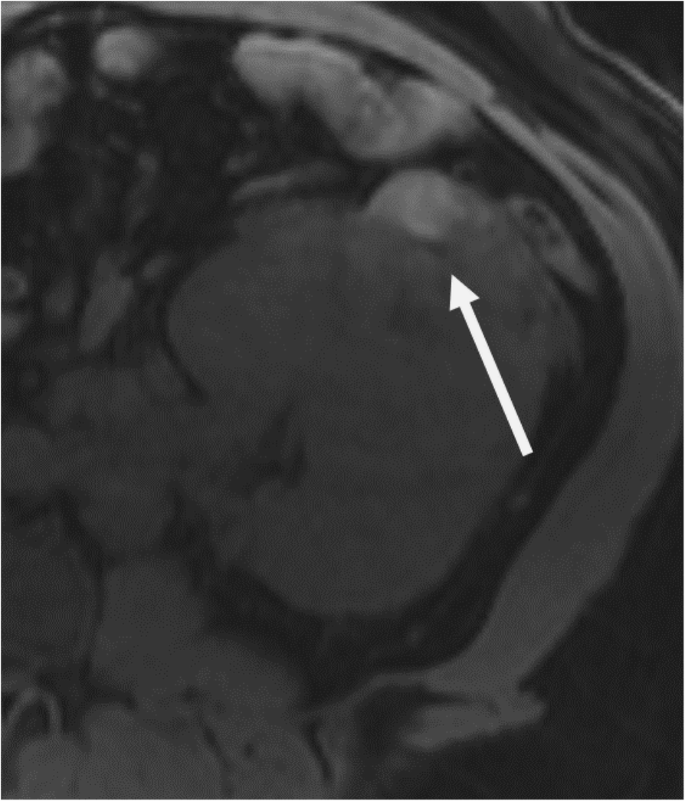

Regarding modality-specific features, all patients had heterogenous tumor enhancement on MRI and CT, and heterogenous T2 signal on MRI (Fig. 3). Of those patients who had diffusion-weighted imaging available for review (n = 11), all had diffusion restriction in the solid portions of the tumor. On MRI, T1 hyperintense hemorrhage was present in 7/12 (58 %) of cases (Fig. 4). No tumors had intravoxel fat on MRI. On CT, no tumors had calcifications. Of the three patients who had an FDG PET/CT, all had high metabolic activity (mean SUVmax 16.4, range 9.6–21.9), as shown in Fig. 5. An example of the gross and histologic features of one of the renal tumors is shown in Fig. 6.

Gross and histology images from a fumarate hydratase-deficient renal cell carcinoma surgical specimen. Gross image (a) shows a renal mass with infiltrative margin (arrowhead), renal pelvis invasion (black arrow) and renal vein invasion (white arrow). Histology image (b) shows tubulopapillary growth of neoplastic cells with high grade nuclear features, invading the renal sinus fat